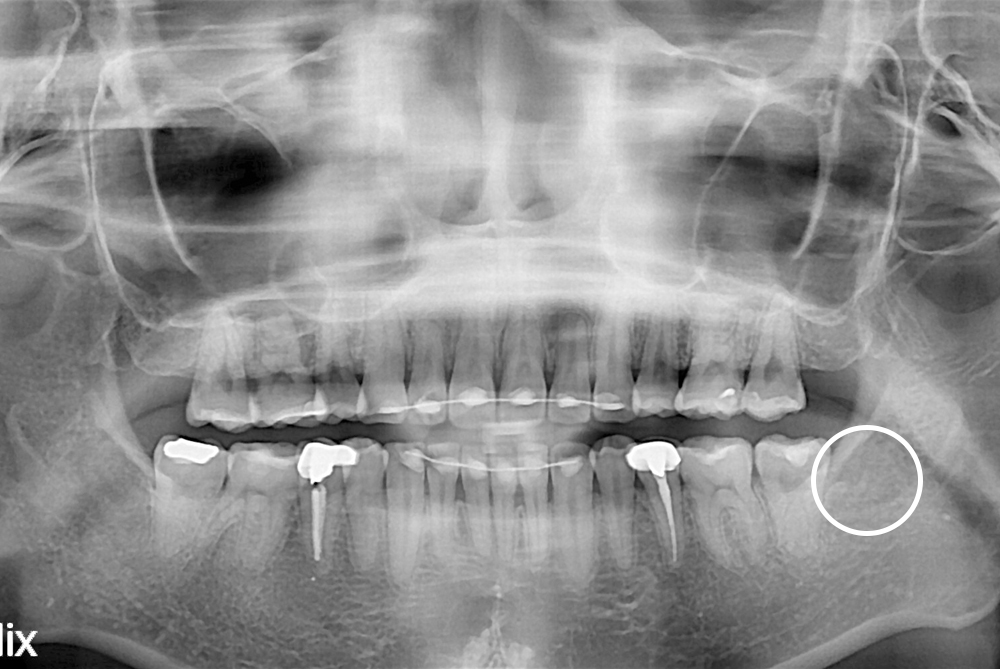

[사랑니] 매복 사랑니 발치

치료전 : 2019-05-14

치료후 : 2019-05-22

세종치과는 구강악안면외과학 박사이신 원장님이 발치하는 치과입니다.